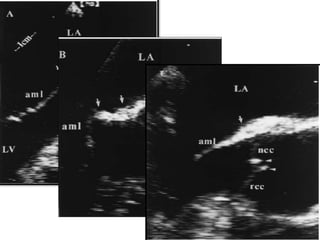

Ankylosing spondylitis

• Thickening of the aortic wall.

• Thickening of the aortic cusps.

• Localised basal AML thickening – suboartic bump.

ROLDAN et al, Aortic root disease and valve disease assosciated with

Ankylosing spondylitis.

JACC 1998;32(5):1397:404.